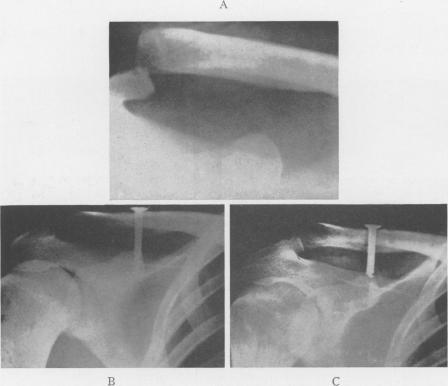

Acromioclavicular Dislocation: End-Results of Screw Suspension Treatment.

Ann Surg. 1948 Jan;127(1):98-111. doi: 10.1097/00000658-194801000-00009.